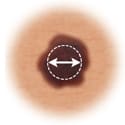

Diameter

|

If the mole's diameter is larger than a pencil's eraser